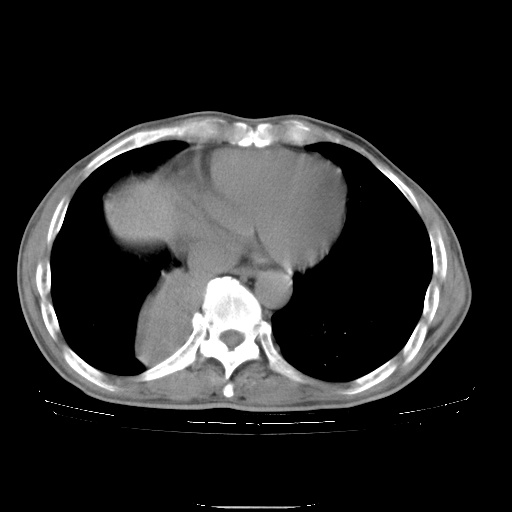

男性患者,63岁。右侧胸背部疼痛2月,加重一周。

考虑:右肺中央型肺癌并右肺下叶不张;两肺尖继发性肺结核。

还有纵隔多处肿大淋巴结及肋骨的改变、两肺多发结节灶。

右下中央型肺癌伴肺内纵膈转移。

右下肺中心型肺癌并肺不张

纵隔淋巴结转移

考虑右中心型肺癌并右下肺不张,肺及纵隔,左肋骨转移。

右肺下叶支气管狭窄闭塞,右下肺不张,气管前间隙淋巴结肿大,两上肺散在分部粟粒灶,沿肺血管支气管束分部,血管支气管束走形较为光滑。考虑右肺中心型肺癌合并肺不张,纵隔淋巴结转移,两上肺癌性淋巴管炎

右肺下叶中心性肺癌并纵隔淋巴结转移,左侧肋骨转移。双肺上叶继发性结核表现。

1)右肺下叶中心性肺癌并纵隔淋巴结转移,两肺转移,左侧肋骨转移。2)双肺上叶继发性结核。

右肺下叶中心性肺癌并纵隔淋巴结及两肺、左侧肋骨转移。双肺上叶继发性结核表现。